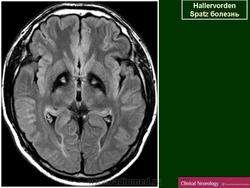

"Глаз тигра"-наглядно и красиво.

Вы правы. Выставил еще более нагладные исллюстрации.